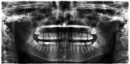

Я сходила к трём врачам, один все сомневался, трогать их или нет, так как они находятся в дёснах и сказал, что лучше будет все же провести операцию по их извлечению, так как места им нет в челюсти. Другой сказал — ваше дело, что с ними делать. Третий стоматолог посмотрел и сказал, что никаких показаний к удалению нет: перитонита нет, и ортодонт не давал показаний, чтобы освободить место в челюсти для других зубов. Также сказал, что надо правильно читать снимки, а зубы на самом деле находятся в челюсти и место там может быть для того, чтобы они вышли. Сказал ждать до 27 лет, они либо прорежутся, либо останутся в зачатках. Сейчас мне 24 года.

Сейчас зубы остановились в росте, опухоль десны спала и никаких признаков прорезывания. Я боюсь, что зубы могут сдвинуться из-за зубов мудрости. Но врач сказал, что они бы давно уже все сдвинулись, если бы хотели и тем более у меня стоит ретейнер.